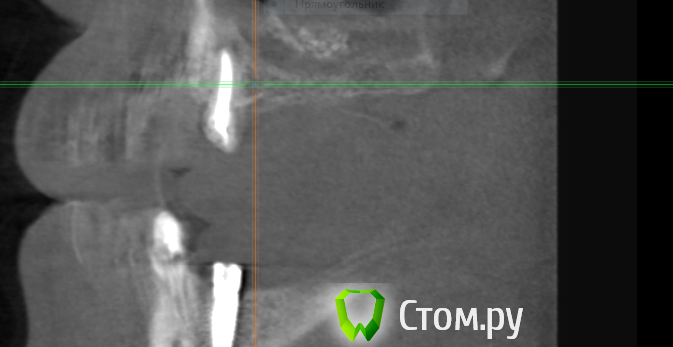

Ljoka- Опубликовано 8 сентября, 2014 Поделиться Опубликовано 8 сентября, 2014 Доктора!Посоветуйте,как решить сложившуюся ситуацию.Пациенту 6 мес.назад был проведен синус во 2 сегменте,3 мес.назад установлен имплант MIS C1.На данный момент,врач проводивший операции переехал в другой город,пациент пришел с повторным КТ.В 3 сегменте-установлен имплант только в позиции 36(по записям в карте-37 поставить не удалось-наблюдаласись боли при постановке,решили ограничиться 36).К сожалению,фото в полости рта нет.имплант в позиции 44-оголена заглушка и подвижная слизистая без гиперимии с вестибулярной стороны 44.На повторный синус пациент идти не хочет(да и нужен ли он)На сколько вероятно поставить один или два импланта путем закрытого синуса в этой ситуации?В области 44 удалять имплант,НКР и ожидать или одновременно имплант+НКР?Спасибо Ссылка на комментарий

Ljoka- Опубликовано 9 сентября, 2014 Автор Поделиться Опубликовано 9 сентября, 2014 Будем делать повторный синус;одномоментно 2 имплантаВ обл.44-по ситуации,наверное отсроченно Ссылка на комментарий